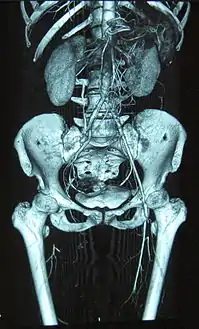

![]() انسداد كامل للشريان الفخذي الأيمن وضيق في الأيسر كما هو موضح في حالة مرض بورغر . انسداد كامل للشريان الفخذي الأيمن وضيق في الأيسر كما هو موضح في حالة مرض بورغر . | |

إن أشعة الشرايين بالصبغة يمكنها أن تُساعد في تشخيص المرض حيث يظهر فيها الشريان متعرج الشكل أو متضيّق أو منسدّ بالكامل وخاصة في الشرايين الطرفية للرجلين واليدين.